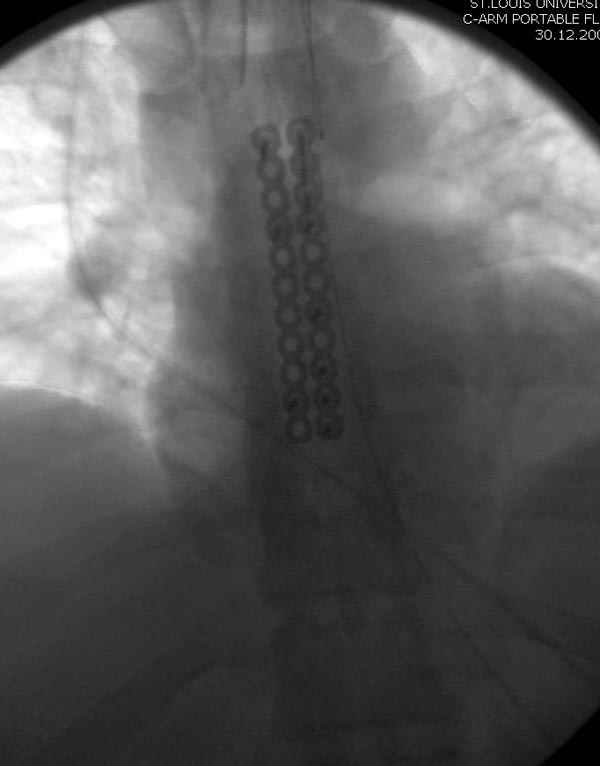

Ложный сустав зафиксирован двумя пластинами 2.4 мм (locking plate) позаимствованными из челюстно-лицевой хирургии, с костной пластикой, все остальные пластины мне показались слишком толстыми, грубые для грудины или отсутсвовали возможности создания угловой стабильности.

Рентген снимки во время операции и последние сделаны на днях.